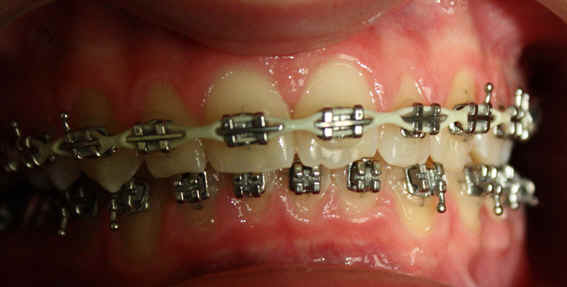

Malpositioned Premolar 13 year-old Caucasian boy

2009/12/19 U .016x.022, L .016 x .022 Niti